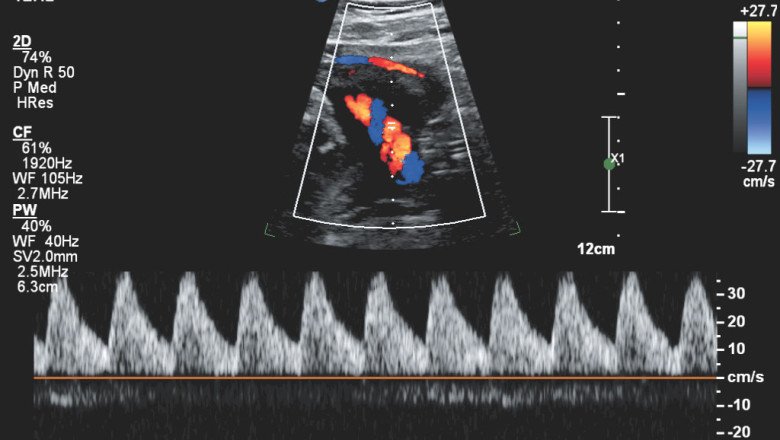

Doppler Ultrasound plays a critical role in the diagnosis and management of cardiovascular diseases. It is used to measure blood flow velocity and direction in the heart and blood vessels. This information can be used to assess the function of the heart valves, detect blockages in the blood vessels, and evaluate the severity of heart disease.